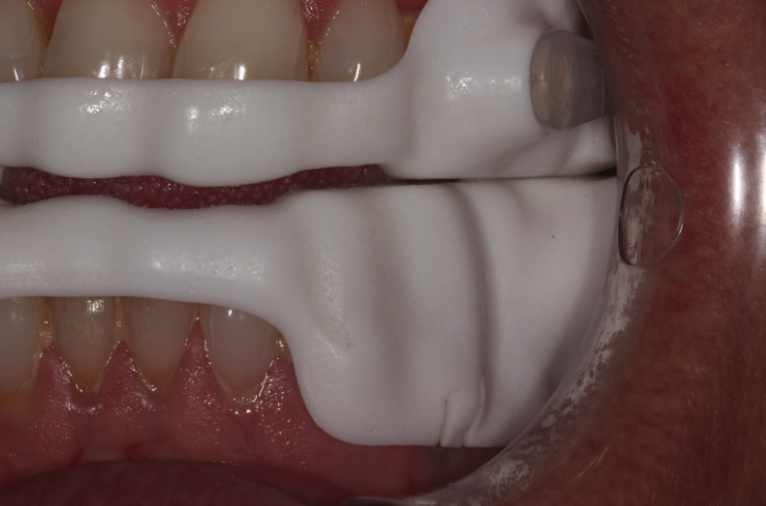

Digital impressions were captured using an intraoral scanner with CS 3600 acquisition software. This was critical because mandibular advancement devices require multiple bite registrations at different protrusion levels — something that digital scanning handles far more accurately than traditional impressions.

The software's undercut tools helped identify where tooth anatomy could be modified — for example, using direct composite attachments to create undercuts that improve appliance retention. Overjet and overbite measurements were recorded at the initial scan for comparison at future reviews to monitor any unwanted tooth movement.

The full arch scans were exported to ResMed, where the 3D model was aligned with a virtual articulator and the Narval CC appliance designed using a completely digital workflow — no physical models, no alginate, no stone.

On fitting day, the device was checked for retention, occlusion, TMJ comfort, connector mechanics, and protrusion accuracy. The fit was accurate and comfortable — reinforcing the benefits of a fully digital impression and design workflow over traditional methods.